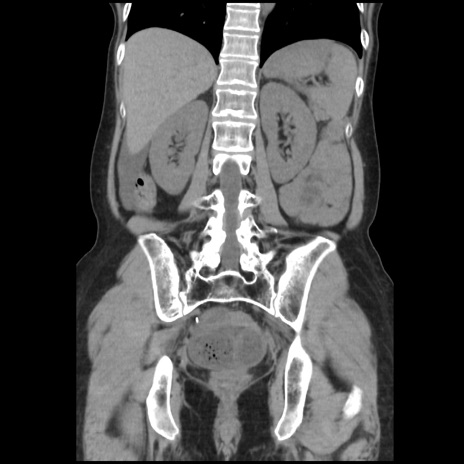

症例32(冠状断像)

【症例】40歳代 女性

【主訴】上腹部痛、嘔気・嘔吐

【現病歴】約9時間前頃から急に上腹部痛、嘔気、嘔吐が出現。改善しないため救急要請。

【既往歴】子宮頚癌(広汎子宮全摘術、放射線療法)、腸閉塞

【身体所見】腹部:平坦、軟、腸雑音亢進、上腹部を中心に腹部全体に圧痛あり。

【データ】WBC 8400、CRP 0.03